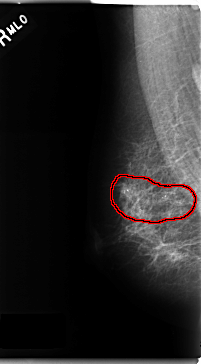

FILE: C_0186_1.RIGHT_MLO.OVERLAY

TOTAL_ABNORMALITIES 1

ABNORMALITY 1

LESION_TYPE CALCIFICATION TYPE PLEOMORPHIC DISTRIBUTION SEGMENTAL

LESION_TYPE MASS SHAPE IRREGULAR MARGINS ILL_DEFINED

ASSESSMENT 5

SUBTLETY 5

PATHOLOGY MALIGNANT

TOTAL_OUTLINES 1

BOUNDARY